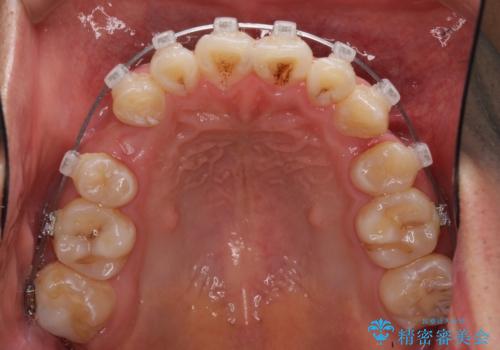

- クリアブラケット

- 前歯の叢生と八重歯を気にして来院された患者様です。

叢生が強く、奥歯の咬合も左右差が大きかったため、上下左右4本を抜歯して、ワイヤー矯正を行うこととしました。

奥歯の咬み合わせを改善したいため、治療期間が長くなりましたが、患者様には辛抱強くお付き合いいただきました。

上下の正中を合わせることもでき、患者様には大変満足していただきました。